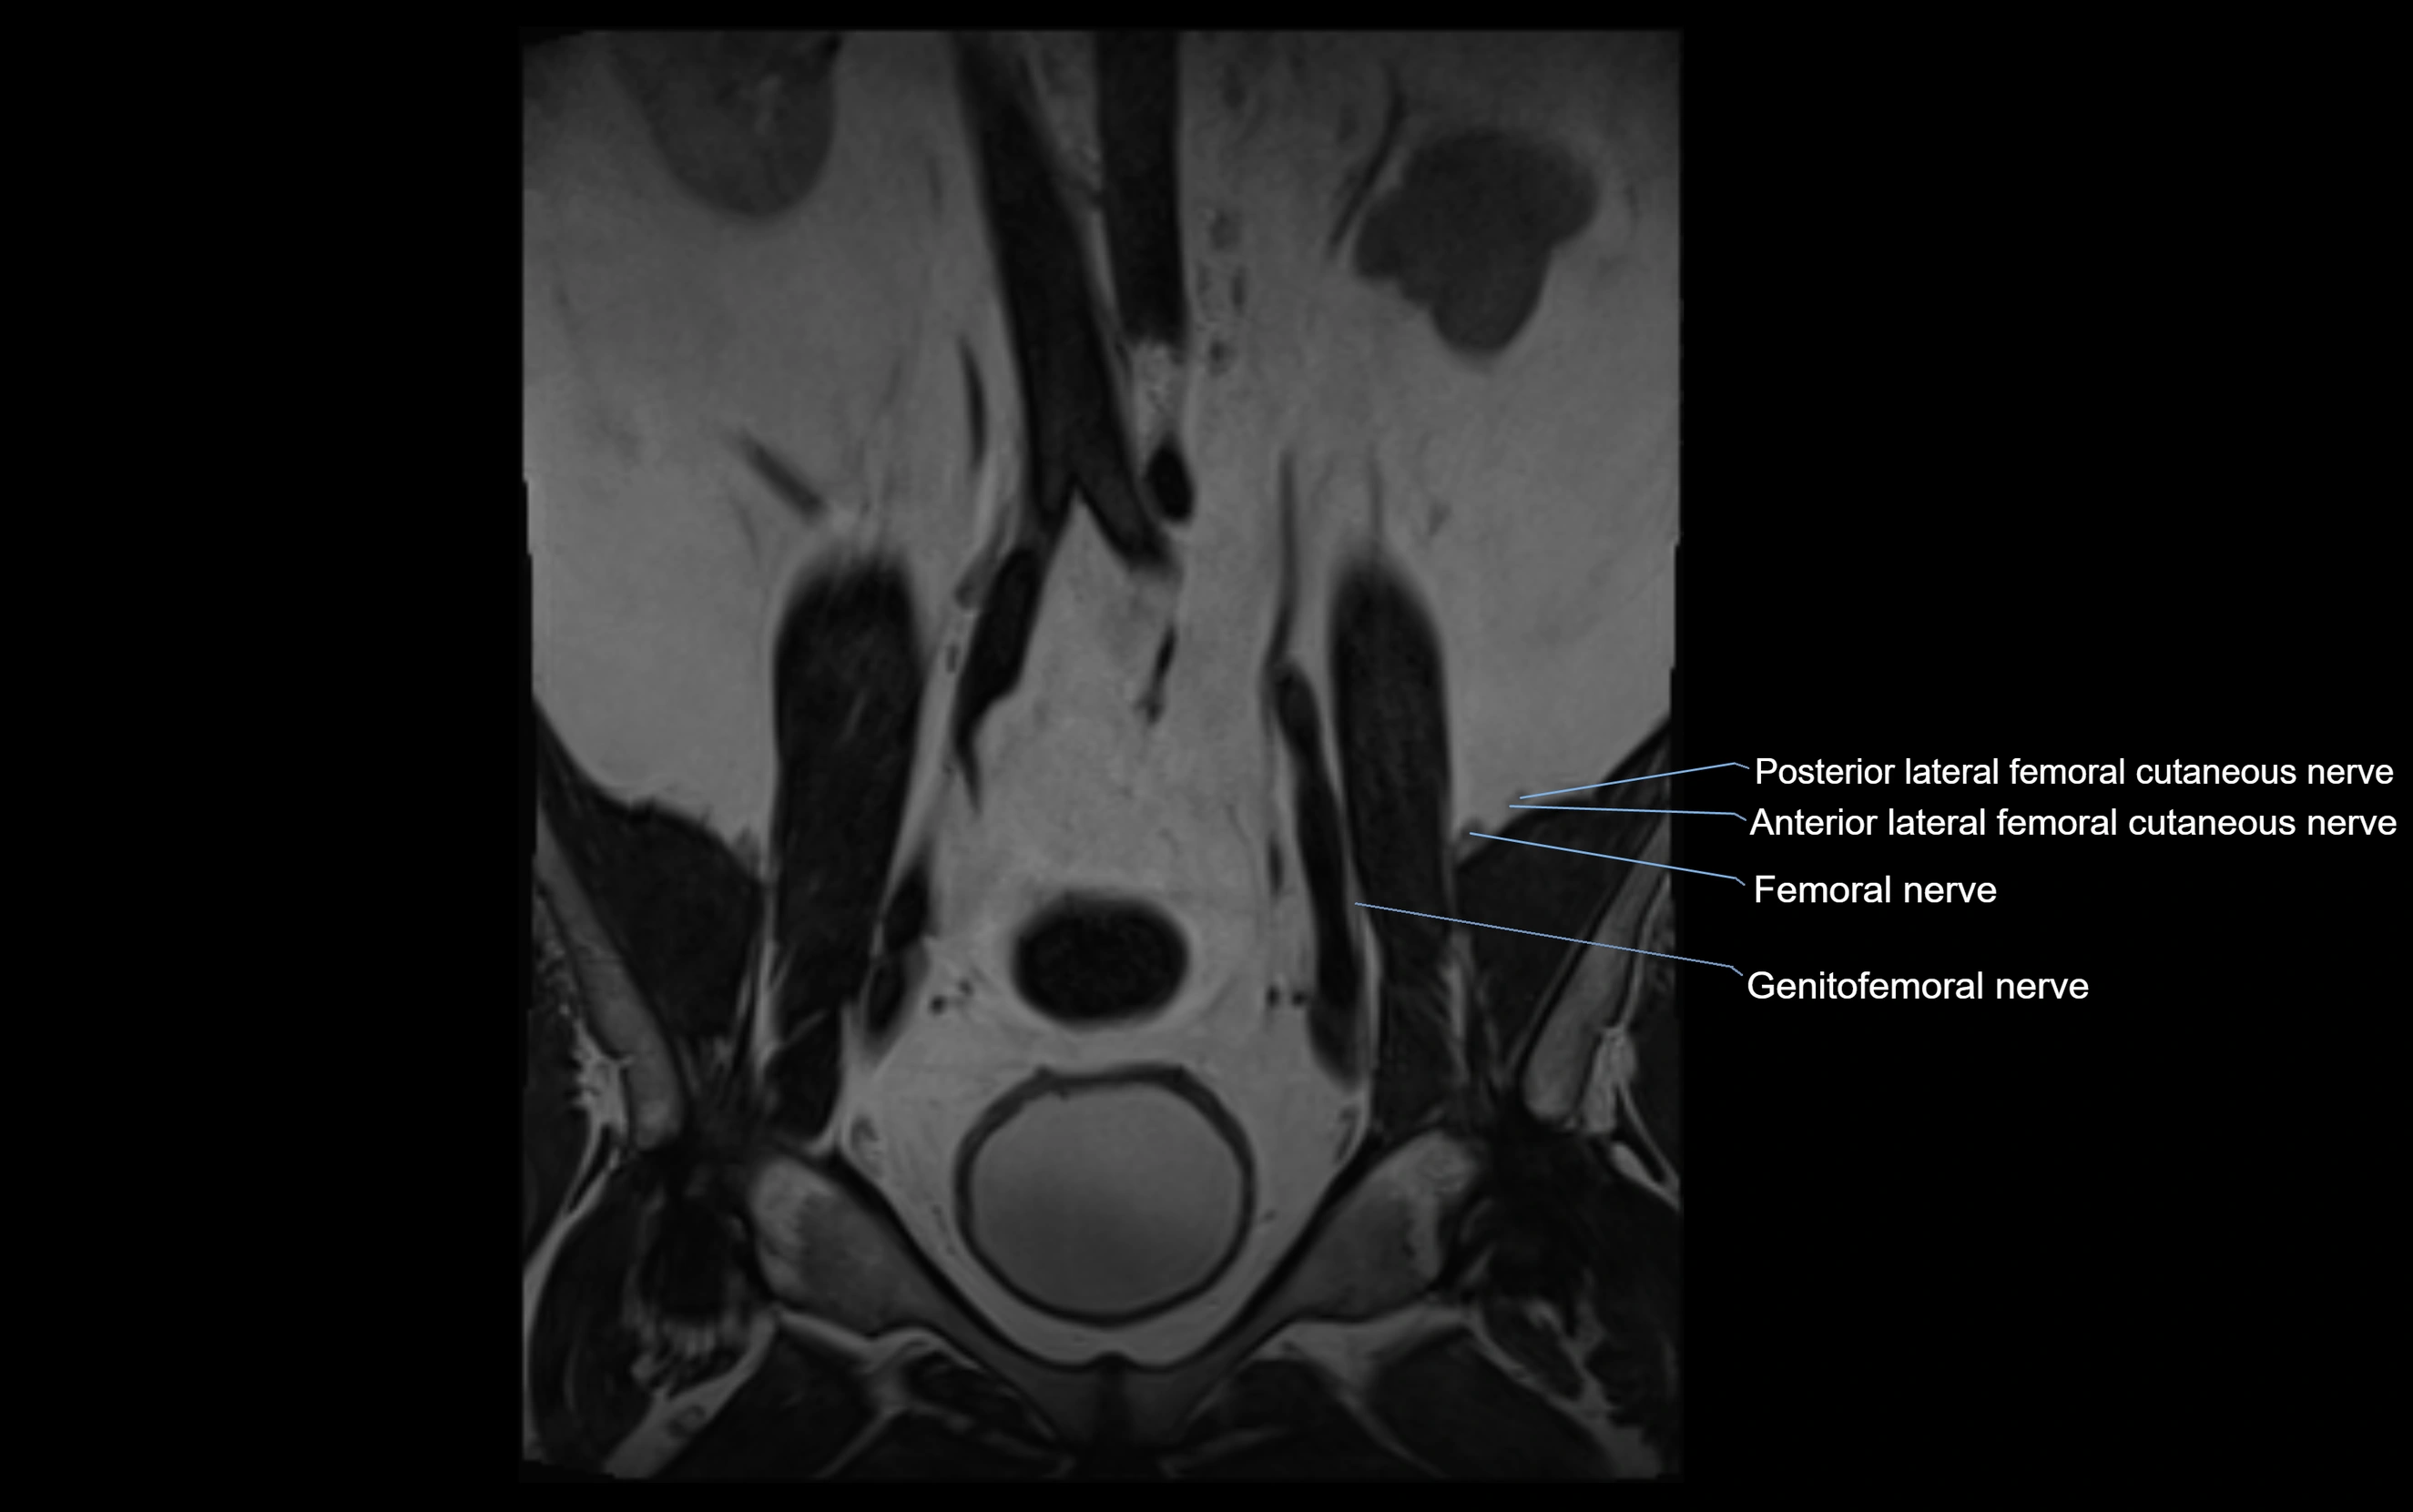

MRI image

image